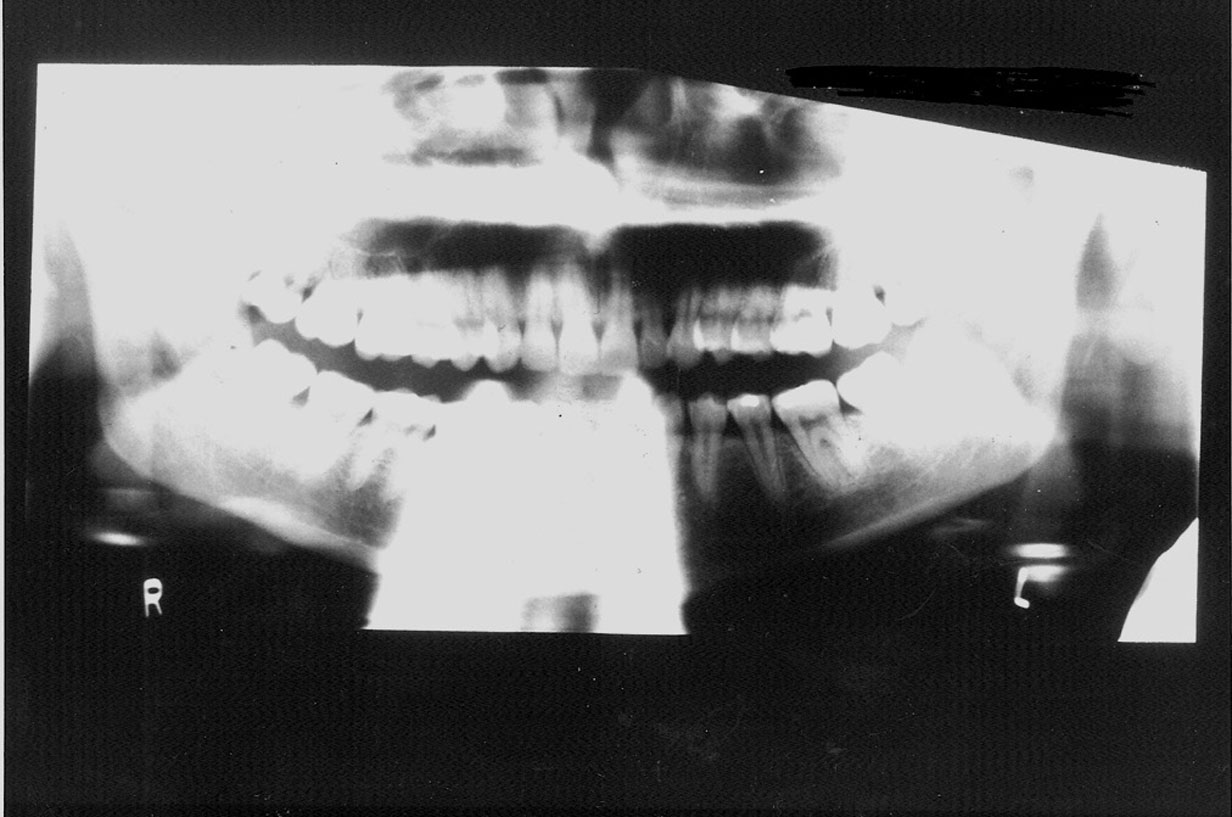

Motion

Vertical, horizontal or compound patient movements and slippage or vibration of the tubehead or film holder can produce a range of artifacts on panoramic films. With conventional films, motion produces generalized unsharpness; with panoramic films, however, motion unsharpness only affects the portion of the film that was being exposed at the time motion occurred. Therefore, depending on the extent and duration of movement, only a small, discreet portion of the exposure may be blurred while the rest of the film is within acceptable limits. Short-duration movement may be difficult to detect because the resulting artifact can look suspiciously like a pathological condition.

The top radiograph in Figure 23 is a normal panograph. The bottom panograph is one that was affected by short-duration movement. Notice how the patient’s left mandible appears to be notched along the upper margin. The notch could easily be interpreted as calcification at an old fracture site when, in reality, it is a movement artifact. Remember, when viewing radiographs, the patient’s left is on the viewer’s right.

Figure 23. Panoramic films - top-normal; bottom - showing movement.

Figure 23